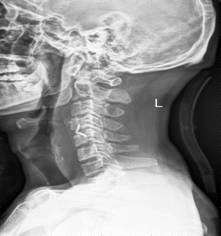

中年男性41歲,因“行走不便2年,加重伴雙手麻木2周”之主訴入院,癥狀主要為:頸部疼痛、僵硬,雙下肢無力、行走不穩(wěn),雙手麻木,協(xié)調(diào)性差,右手握筆困難。入院查體:步態(tài)不穩(wěn),C3-C7壓痛、叩擊痛,肢痛溫覺減退,雙上肢肢肌力5-級,雙下肢肌力4-級,肌張力增高,雙下肢腱反射亢進(jìn),病理征(+),行頸前路小切口突出椎間盤切除、前路頸椎橋形鎖定植骨融合(ROI-C假體),無需前路鋼板,術(shù)后四肢麻木明顯緩解,右上肢精細(xì)動作明確增強(qiáng),可寫字,行走不穩(wěn)消失,肌力基本正常,頸部活動度無明顯受限。(圖1、圖2)

圖2:術(shù)后頸椎X線提示頸椎橋形鎖定融合居中,椎間隙高度恢復(fù)正常,融合良好。